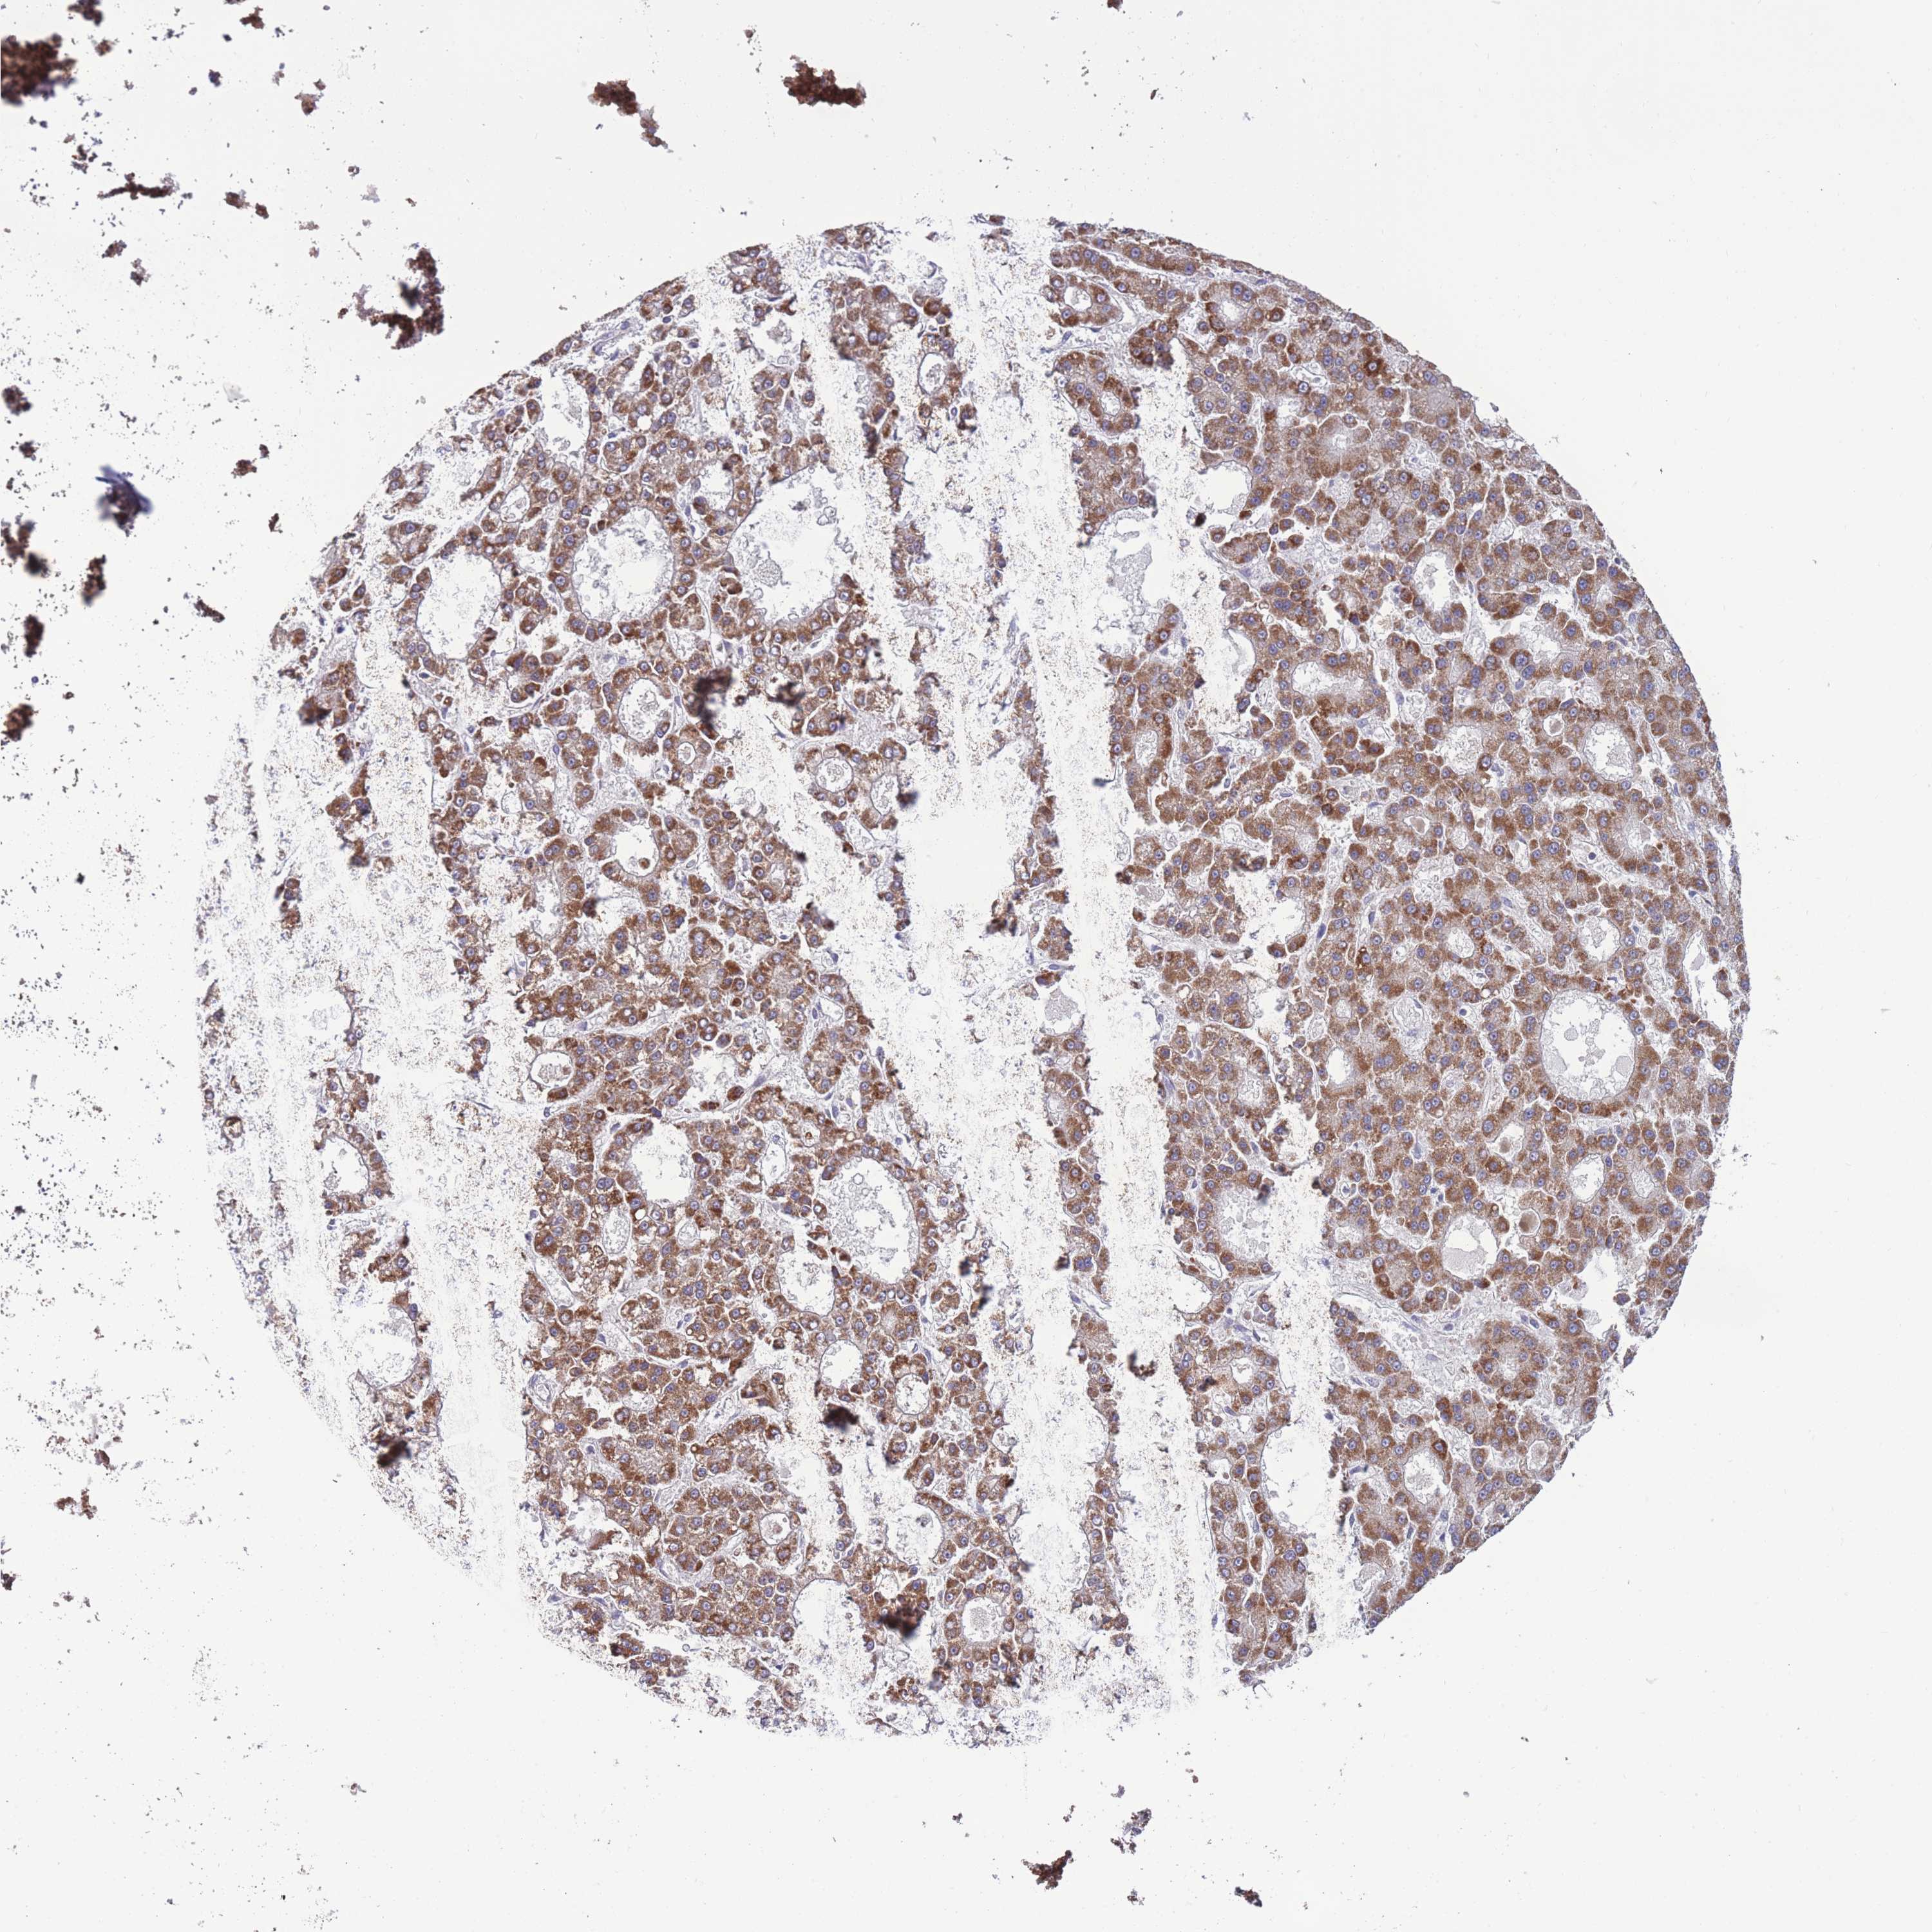

LIVER CANCER - Protein expressioni

A mouse-over function shows sample information and annotation data. Click on an image to view it in a full screen mode. Samples can be filtered based on level of antibody staining by selecting one or several of the following categories: high, medium, low and not detected. The assay and annotation is described here.

Note that samples used for immunohistochemistry by the Human Protein Atlas do not correspond to samples in the TCGA dataset.

Antibody stainingi

Antibody staining in the annotated cell types in the current human tissue is reported as not detected, low, medium, or high, based on conventional immunohistochemistry profiling in selected tissues. This score is based on the combination of the staining intensity and fraction of stained cells.

Each image is clickable and will lead to virtual microscopy that enables deeper exploration of all samples and also displays staining intensity scores, fraction scores and subcellular localization as well as patient and tissue information for each sample.

Antibody HPA049981

Staining

High

Medium

Low

Not detected

Intensity

Strong

Moderate

Weak

Negative

Quantity

>75%

75%-25%

<25%

None

Location

Nuclear

Cytoplasmic/membranous

Cytoplasmic/membranous,nuclear

Cholangiocarcinoma

Carcinoma, Hepatocellular, NOS